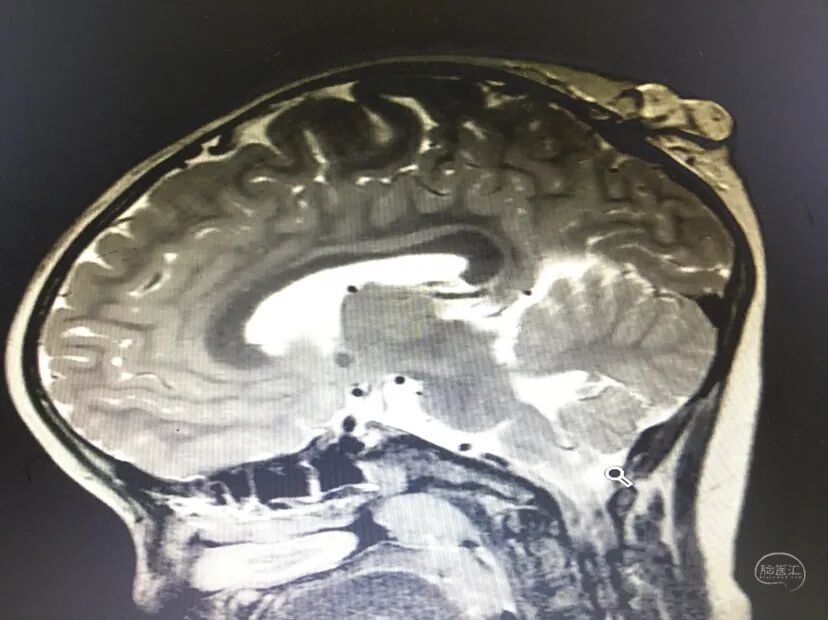

术前情况

术中情况

儿童脑膜脑膨出是一种罕见的先天性疾病,病因不明,可能与胚胎时期神经管发育不良,中胚叶发育停滞,使颅骨发育缺陷出现颅裂,脑膜或脑膜脑组织经颅骨缺损处疝出颅外有关。临床表现为囊性肿物与头部相连,可在出生时发现,也可在出生几个月或几年后发现,哭闹或咳嗽时肿物增大,局部可扪及骨缺损的边缘。修补手术注意严密修补硬脑膜防脑脊液漏皮下积液。